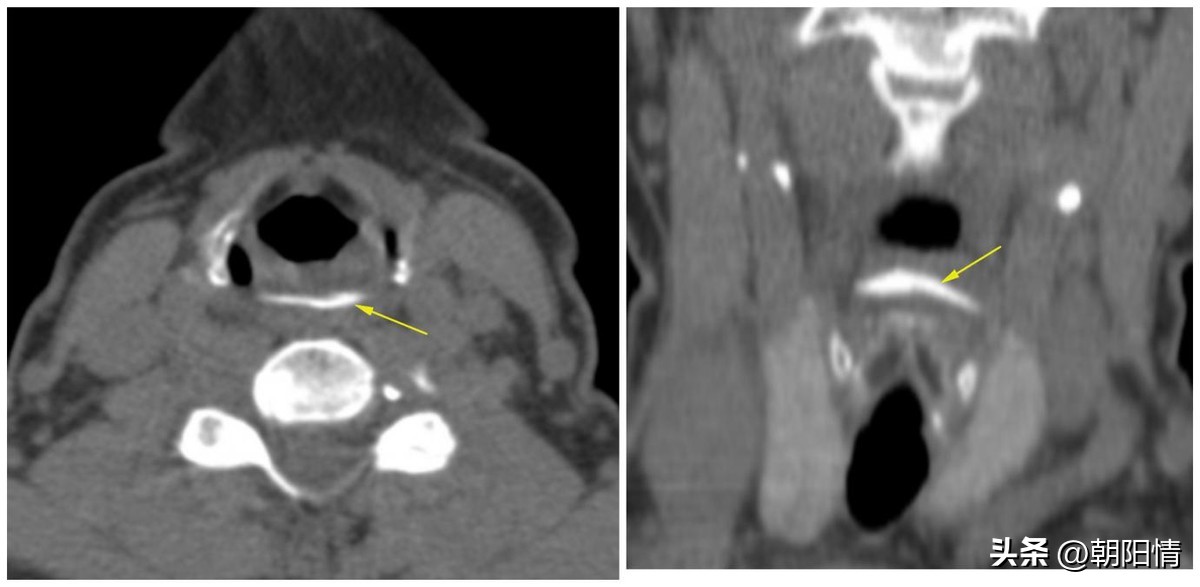

Case3:食管入口梨状窝水平横行异物,需与喉软骨相鉴别。

(1)颈段食管异物

随着多层螺旋CT的发展及其重建技术的应用,多层螺旋CT可以明确消化道异物的诊断,了解异物的大小、形态及异物与周围组织的关系,观察食管、肠管周围是否存在并发症。为临床提供丰富的诊疗信息,具有重要的参考价值。